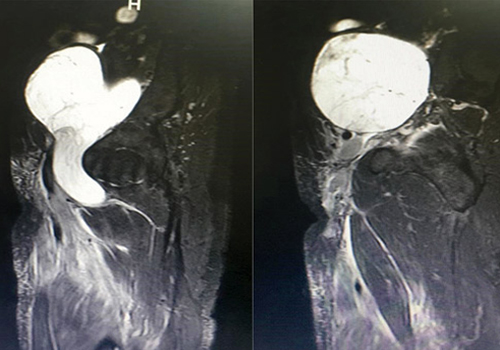

والذي قال إن المريض راجع المستشفى وهو في حالة صحية سيئة للغاية نتيجة للأعراض المرضية التي يعاني منها ورفض كثير من المستشفيات إجراء أي تدخلات جراحية وعلاجية لها نظراً لخطورة وصعوبة الحالة، حيث خضع للفحص السريري وعمل الفحوصات والأشعة المقطعية والرنين المغناطيسي MRI، وقد أظهرت النتائج وجود ورم حجمه 11x20 سم بمنطقة البطن والحوض من الجهة اليسرى أدى لضغط على الأوردة العميقة والرئيسة الموصلة إلى الرجل وتجلط الدم الموجود فيها.